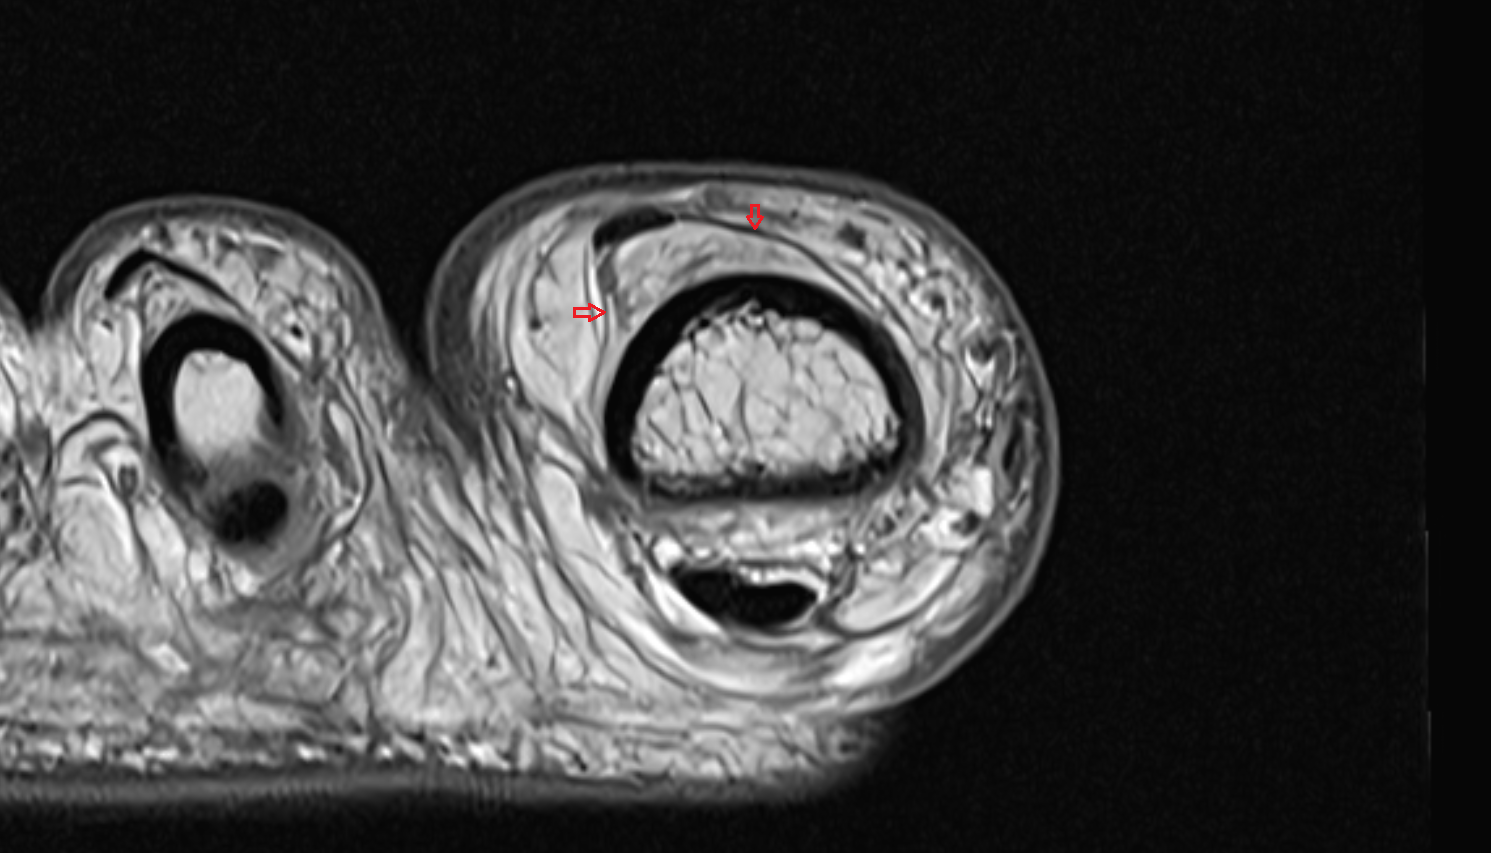

- Peripheral zone of prostate

- Anterior Fibromuscular Stroma of prostate

- Central zone of prostate

- Transitional zone of prostate